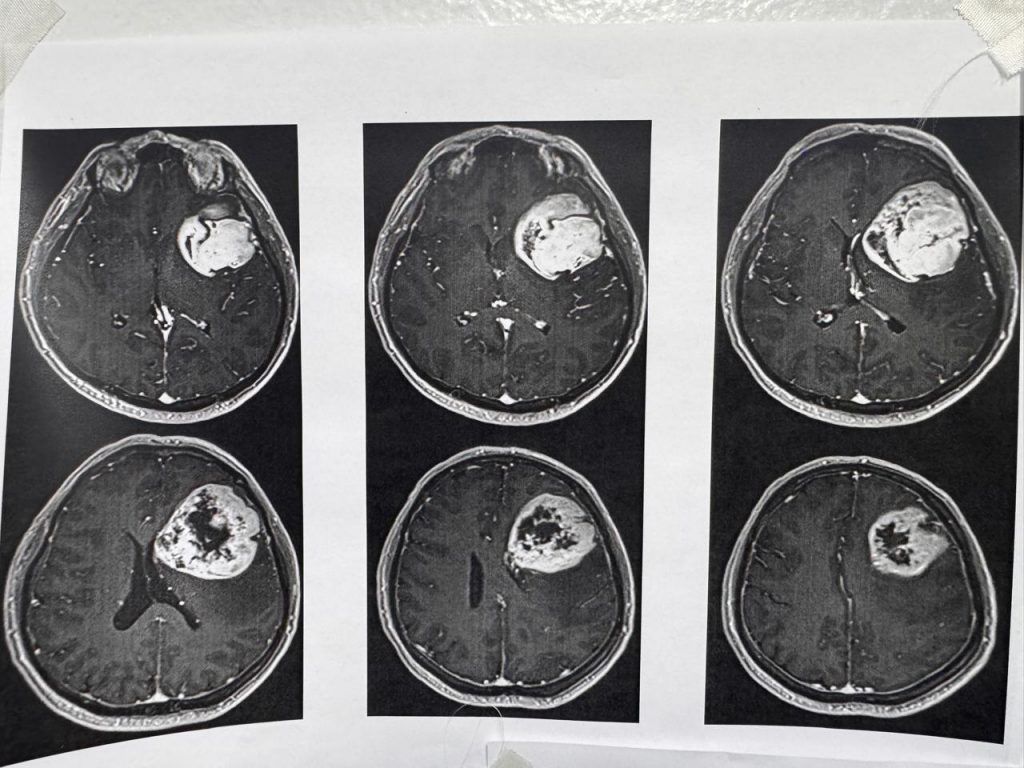

● Gracias al profesionalismo del equipo del servicio de neurocirugía del ISSSTE, un derechohabiente de 54 años recuperó habilidades de lenguaje y motricidad que perdió en dos meses debido a un tumor cerebral.

Una semana después del procedimiento de alta complejidad, el derechohabiente fue dado de alta para completar su recuperación en casa luego de que especialistas en neurología y de diversas áreas retiraron exitosamente un tumor cerebral a un derechohabiente de 54 años, quien permaneció despierto durante el procedimiento que duró siete horas en el Centro Médico (CMN) “20 de Noviembre”, perteneciente al Instituto de Seguridad y Servicios Sociales de los Trabajadores del Estado (ISSSTE).

El neurocirujano a cargo de la operación, Cuauhtémoc Gil Ortiz Mejía, informó que, en coordinación con la especialista en Neuropsicología, se decidió practicarle al derechohabiente un procedimiento llamado craneotomía con paciente despierto, a fin de regresarle las habilidades de lenguaje y motricidad que perdió paulatinamente en un lapso de dos meses por la presencia del tumor.

“El procedimiento realizado en agosto fue de alta complejidad, tuvo una duración de siete horas y se utilizó tecnología de vanguardia, como un neuronavegador cerebral,un microscopio quirúrgico, aspirador ultrasónico, craneotomo eléctrico, neuroestimulador eléctrico de la corteza cerebral, neuromonitoreo transoperatorio y equipo médico de neuroanestesia”, detalló.

Para determinar la realización de este procedimiento y conocer el orígen de los síntomas, explicó, el equipo médico del Instituto le realizó al derechohabiente estudios de tomografía y resonancia magnética.

“Se realizó tomografía de cráneo y, ante los hallazgos, se le practicó una resonancia magnética; posteriormente, se le detectó un tumor de características malignas en la región frontal premotora izquierda”, detalló.

El neurocirujano y miembro del Comité de Cirugía de Epilepsia y de Neurooncología, informó que el paciente recuperó inmediatamente sus funciones luego de la cirugía, por lo que fue dado de alta una semana después de haber sido intervenido para completar su convalecencia en casa, antes de continuar con el tratamiento complementario.

Este procedimiento se suma al realizado en julio de este año, en el que la paciente Yolitzin Salgado, de 34 años, también recuperó su salud y calidad de vida, gracias al profesionalismo del personal médico del Instituto.

Durante la intervención participaron el neuroanestesiólogo, Jesús García Cuevas; la Neuro psicóloga, Erika Graciela Meza Dávalos; así como los residentes de neurocirugía Francisco Castañeda Aguayo, Carlos Alberto Razo Vite, Salvador Guillermo Cabrera Medina; el psicólogo Diego Islas Almazán; los residentes de Anestesia, Daniela Santamaría Solís, Oscar Chimal García; la enfermera instrumentista, Carolina Reyes Iturbide; y la enfermera circulante, Gabriela López Montelongo.